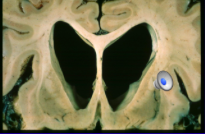

appearance of Huntington brain

flattening of normal convex curve of lateral ventricles - due to loss of ganglia from caudate nucleus